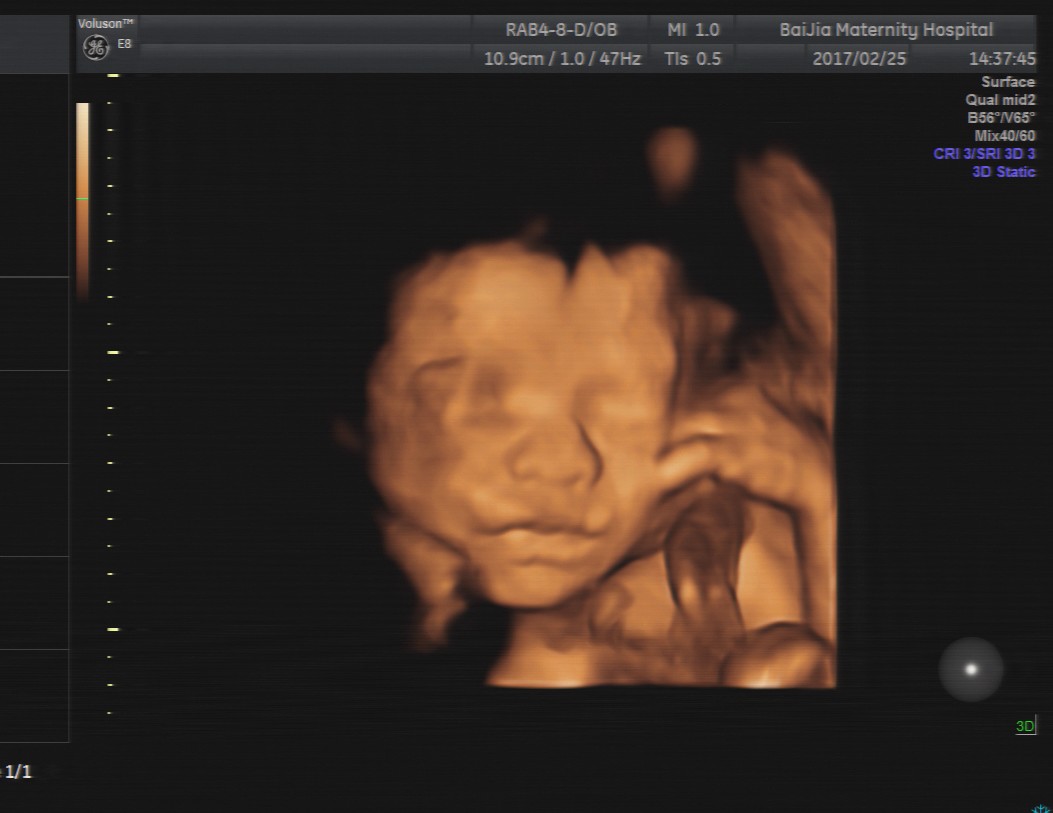

四维彩超能直接观察到胎宝宝发育及在宫内的活动情况,这让很多孕妈咪都很期待做四维彩超检查,但清晰的四维成像对孕周有着严格的要求, 那么, 上海做四维彩超的最佳时间是多

四维彩超能直接观察到胎宝宝发育及在宫内的活动情况,这让很多孕妈咪都很期待做四维彩超检查,但清晰的四维成像对孕周有着严格的要求, 那么,上海做四维彩超的最佳时间是多少周呢?

理论上来讲,孕20—24周是做四维彩超的最佳时间,这个时期是胎儿的快速发育时期,胎儿的基本结构已经形成。同时,适中的胎儿大小及羊水量,给胎儿提供了较大的活动空间,有利于全方位观察胎儿的活动状态。

除了观察胎儿的活动情况,孕中期对胎儿做四维彩超的主要目的是筛查胎儿结构畸形。

四维彩超仅仅是一些孕妈咪为了便于记忆的叫法,医生一般将这次检查叫做“系统胎儿超声检查”或“大结构畸形筛查”,它会对胎儿的结构进行系统性的筛查。

当然根据筛查分级不同,检查项目也会有所不同,但基本都包括胎儿颅骨、脊柱、胸腔、肾脏等基础结构检查。《《《:可点击此处,了解四维彩超不同分级的具体检查项目